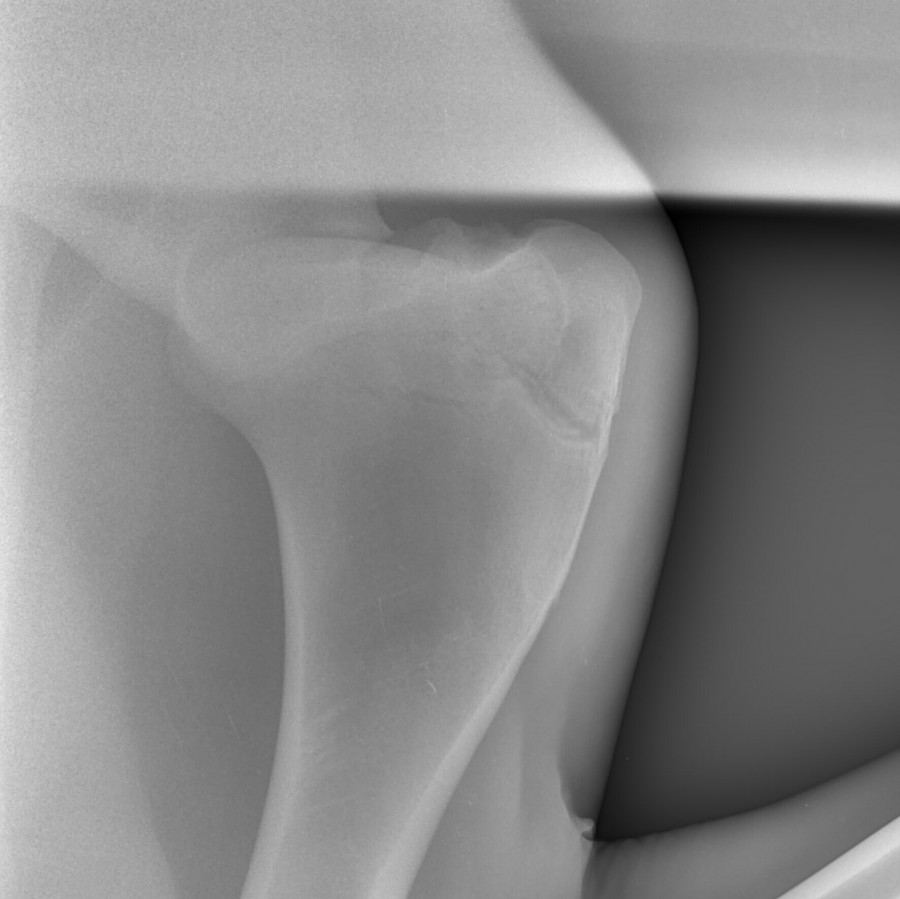

anokilie oui effectivement on a fait des radio. Non j'ai pas encore expliqué, si sur ma page uniquement.

Donc Voici les radios de granola, la première le 2mai, la deuxième le 23mai. D'après le veto la fracture se remet bien. On doit faire une radio dans 1mois. Donc il a le droit de sortir du box, même s'il trotte ou galope ce n'est pas grave mais faut éviter qu'il face le fou pour risquer de se refaire mal ou même de tomber.